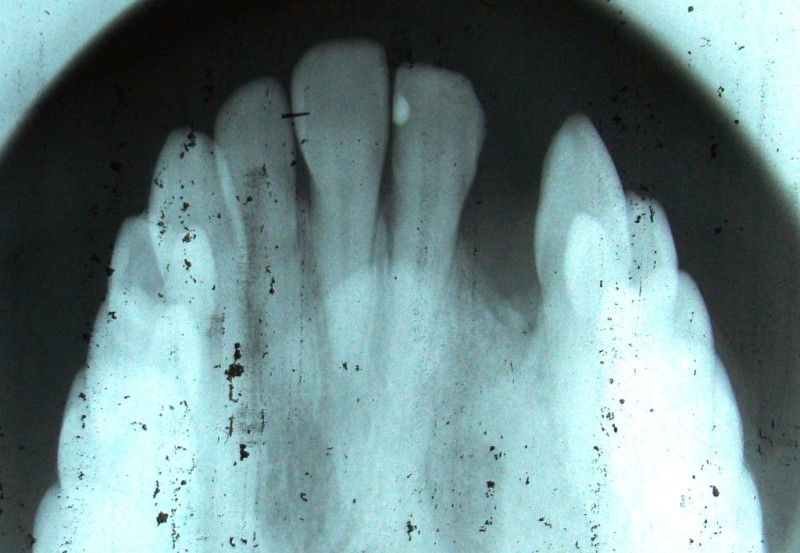

Alveolar Cleft (Defect in the Upper Jaw) Repaired with a Hip Bone Graft

After Bone Graft